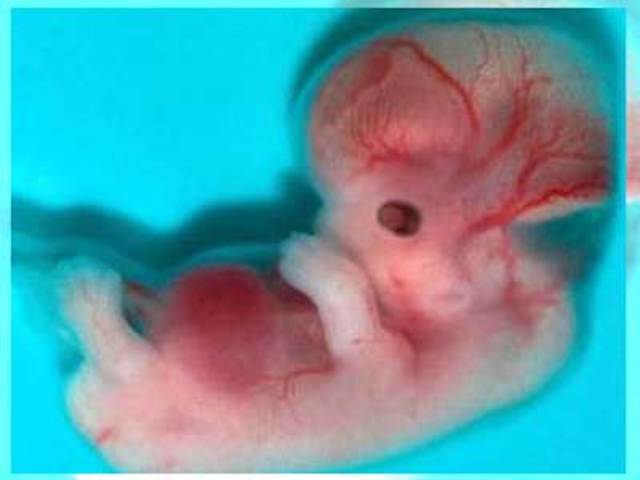

• Comienzan los esbozos de las extremidades, la boca y las mandíbulas son visibles.

Comienzan los esbozos de las extremidades, la boca y las mandíbulas son visibles.

El embrión mide 4mm de longitud; ésta se mide desde el extremo de la cabeza hasta el talón. Cada día la longitud aumenta 1mm hasta el día 55 de gestación. Después crece 1,5mm diario